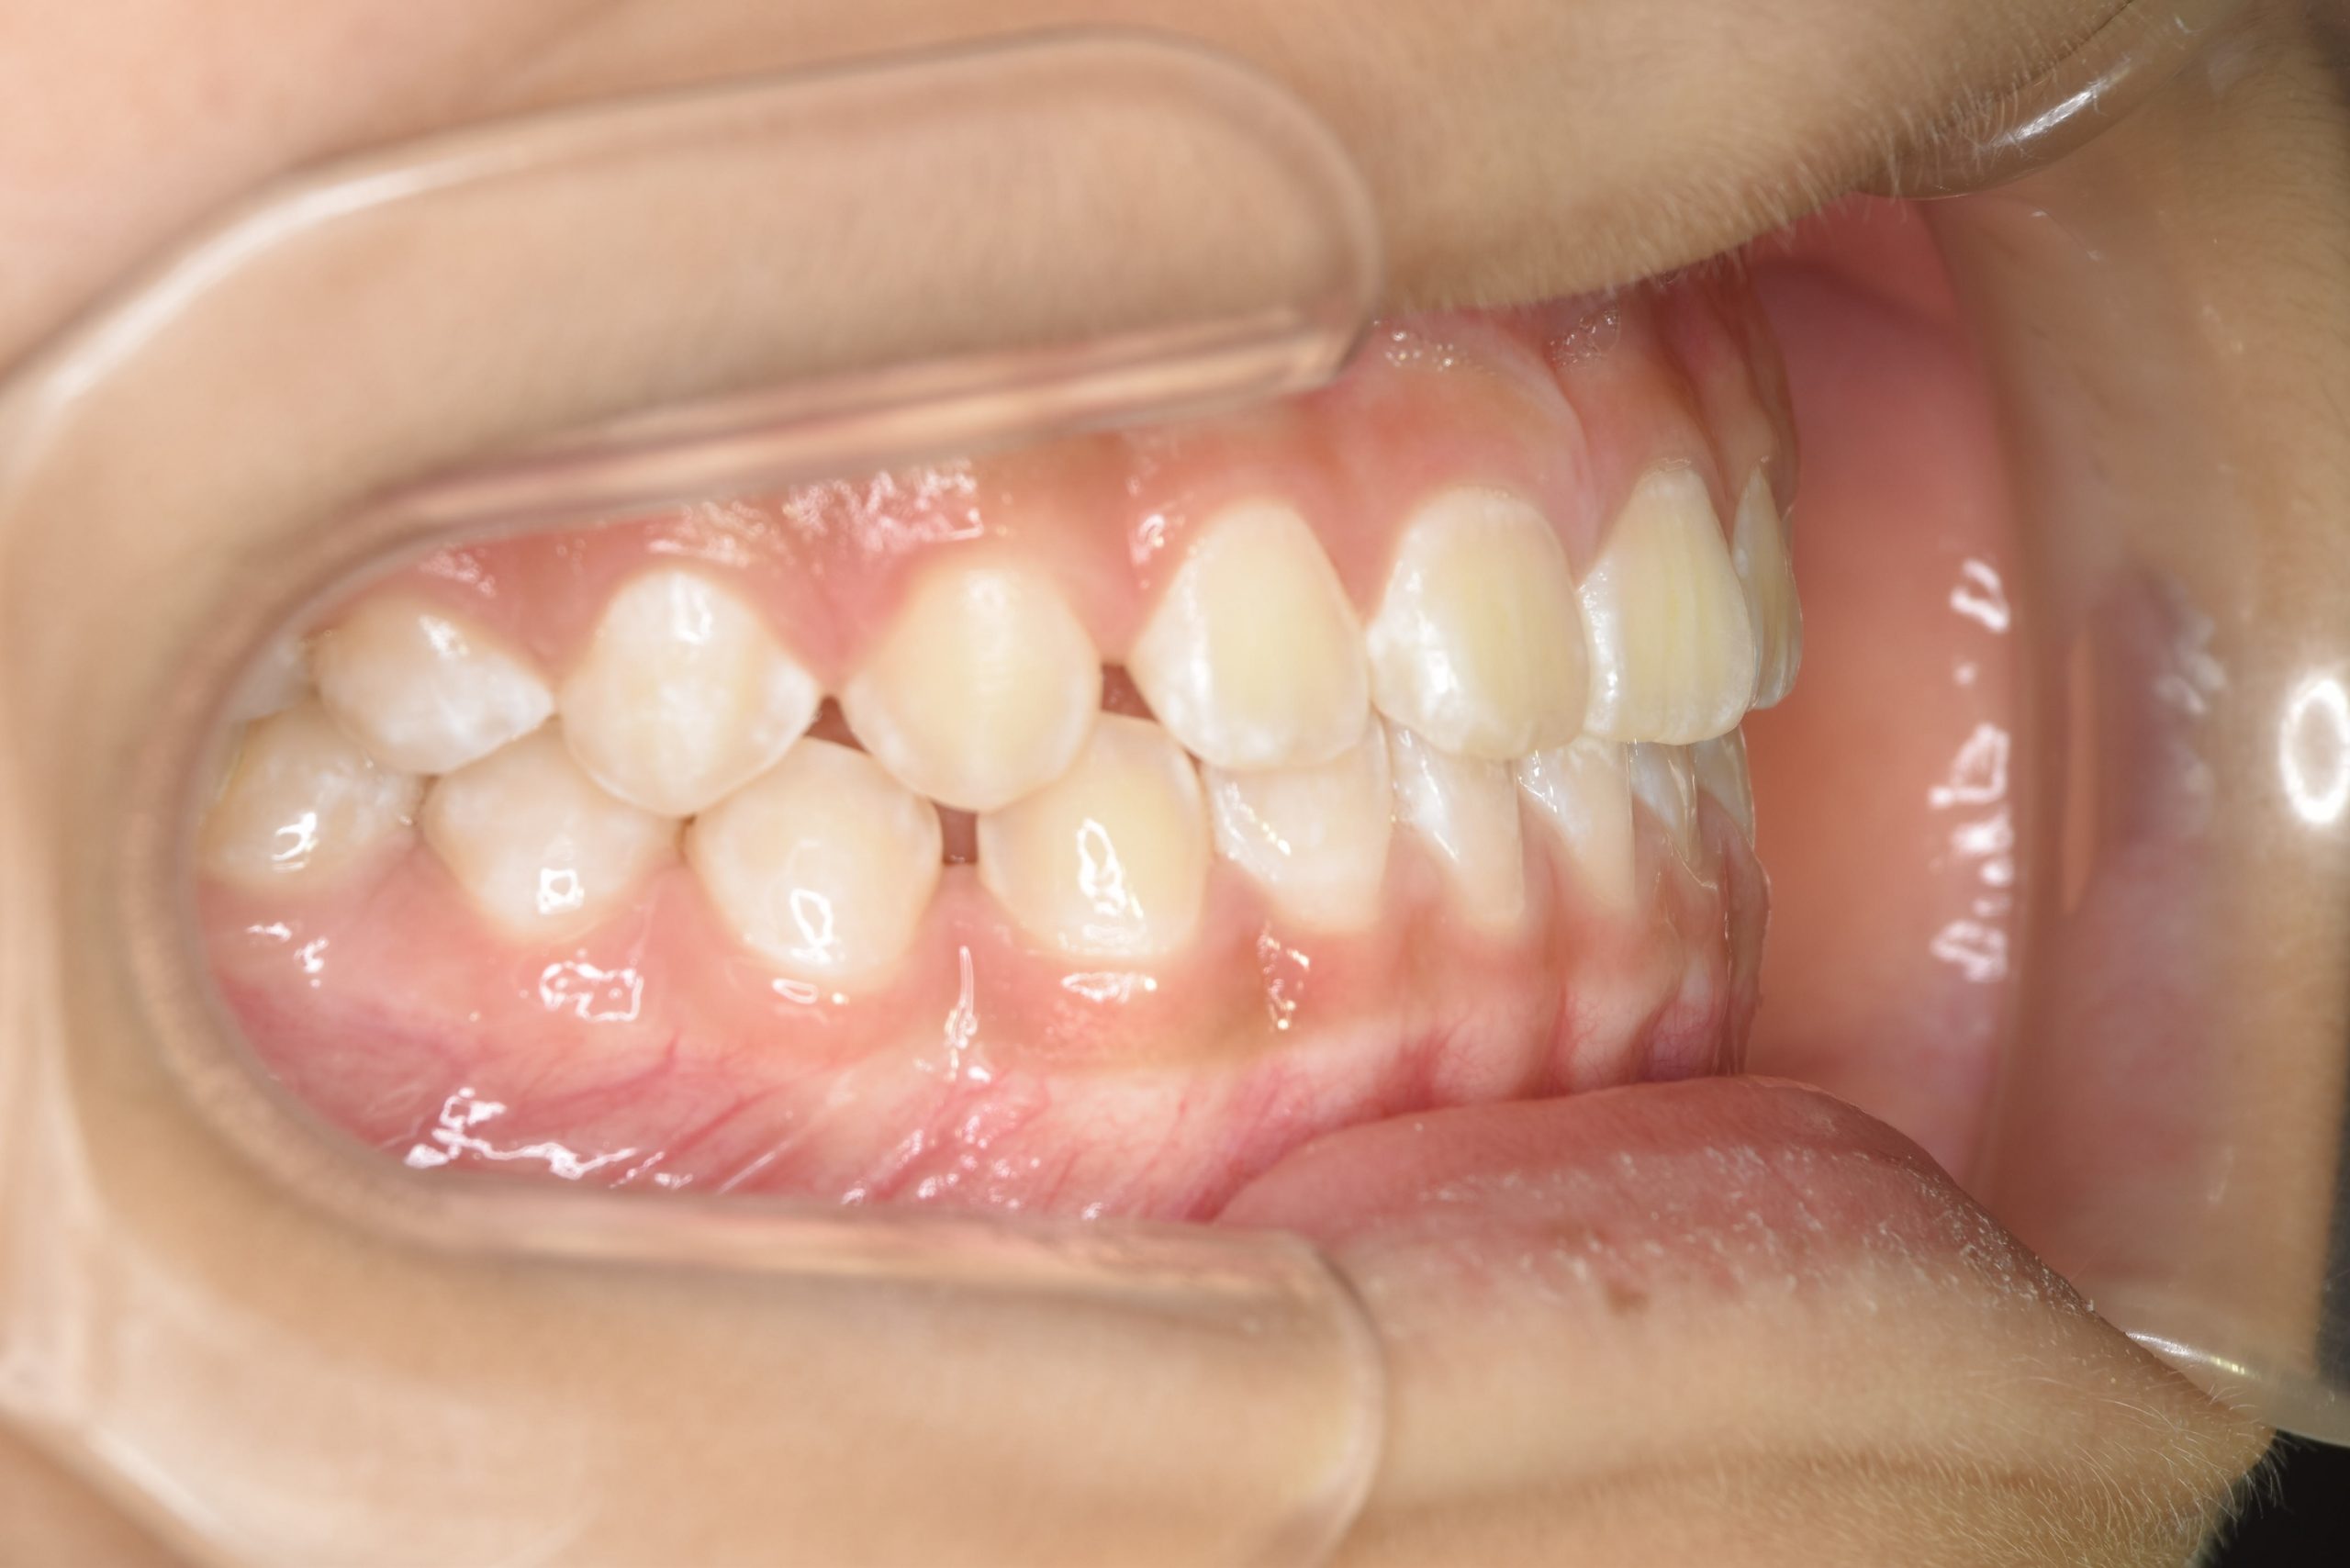

アフター

子どもの矯正治療|症例_858

施術内容 上顎急速拡大装置と下顎リンガルアーチを用いて上下顎骨を拡大した。

上顎前方牽引装置を用いて上顎骨を前方に成長促進させた。

その後マウスピース型矯正装置で歯牙を配列し良好な咬合を獲得した。

治癒期間 1年6か月 ※経過観察含む